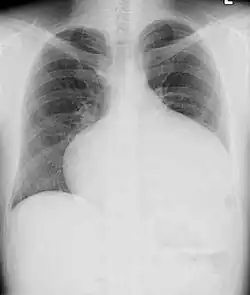

Adults with an uncorrected ASD present with symptoms of dyspnea on exertion (shortness of breath with minimal exercise), congestive heart failure, or cerebrovascular accident (stroke). They may be noted on routine testing to have an abnormal chest X-ray or an abnormal ECG and may have atrial fibrillation. If the ASD causes a left-to-right shunt, the pulmonary vasculature in both lungs may appear dilated on chest X-ray, due to the increase in pulmonary blood flow.[36]

Echocardiography

In transthoracic echocardiography, an atrial septal defect may be seen on color flow imaging as a jet of blood from the left atrium to the right atrium.

If agitated saline is injected into a peripheral vein during echocardiography, small air bubbles can be seen on echocardiographic imaging. Bubbles traveling across an ASD may be seen either at rest or during a cough. (Bubbles only flow from right atrium to left atrium if the right atrial pressure is greater than left atrial). Because better visualization of the atria is achieved with transesophageal echocardiography, this test may be performed in individuals with a suspected ASD which is not visualized on transthoracic imaging. Newer techniques to visualize these defects involve intracardiac imaging with special catheters typically placed in the venous system and advanced to the level of the heart. This type of imaging is becoming more common and involves only mild sedation for the patient typically.